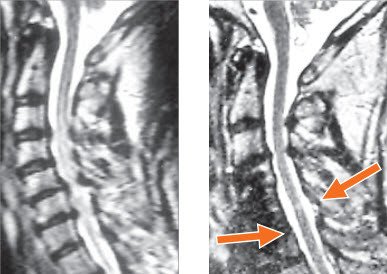

Bei Einengung des Nervenkanals ist das Rückenmark mit seiner wichtigen Steuerungsfunktion bedroht. Hier ist die Operation notwendig, um mögliche Lähmungen abzuwenden. Allerdings kann auch im Fall einer erfolgreichen Entlastung des Rückenmarks keine sichere Aussage über die Erholung der vorhandenen Störungen gemacht werden. Diese ist im Einzelfall abhängig von Ausmass und Dauer der Druckwirkung.

Ist bei der degenerativen Halswirbelsäule geplant, die Stellung der Halswirbelsäule zu korrigieren oder das Rückenmark zu entlasten, weil der Nervenkanal von vorne eingeengt ist, wird ein vorderer Zugang gewählt. Durch einen quer oder längs verlaufenden Hautschnitt kann dabei auf die Vorderseite der Halswirbelsäule eingegangen werden. Dadurch kommen die Vorderseiten der Wirbelkörper und die Bandscheiben ins Blickfeld. Je nach Eingriff wird hier die Bandscheibe isoliert oder zusammen mit dem Wirbelkörper entfernt. Dies ermöglicht den Zugang zum Nervenkanal. In dieser Phase muss besonders auf die Schonung des Rückenmarks geachtet werden.